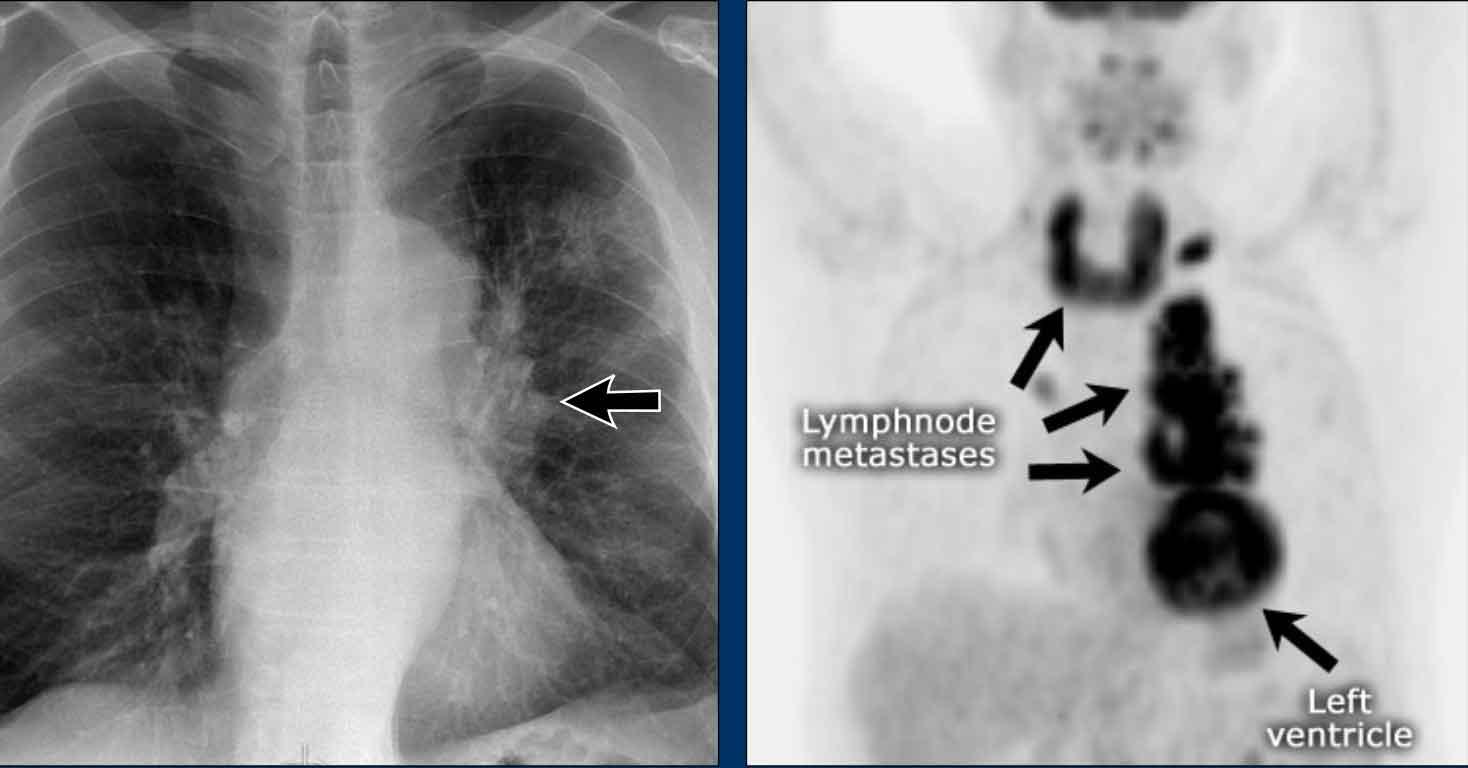

Dịch chuyển đường azygô-thực quản (2) – Hạch to dưới carina

Một nguyên nhân thường gặp gây dịch chuyển đường azygô-thực quản là hạch to dưới carina (trạm 7).

Trên phim X-quang ngực, lưu ý hình ảnh đường azygô-thực quản bị đẩy lên trên ngay dưới carina, phù hợp với hình ảnh hạch bạch huyết dưới carina to (mũi tên đen).

Ngoài ra còn thấy hạch to cạnh khí quản phải, đẩy dải cạnh khí quản phải (mũi tên trắng) và làm lệch khí quản sang trái.

Tiếp tục với hình ảnh PET-CT…

Hình ảnh PET

- PET-CT cho thấy hình ảnh hạch to tăng chuyển hóa lan rộng ở trung thất và vùng cổ, rõ ràng hơn so với trên phim X-quang ngực.

- Các hạch bạch huyết vùng cổ có liên quan — đây là phát hiện quan trọng vì chúng có thể tiếp cận được để sinh thiết.

Tiếp tục với hình ảnh CT và siêu âm…

Hình ảnh CT

- CT có thuốc cản quang cho thấy hạch to dưới carina kích thước lớn, đẩy lệch ngách azygô-thực quản và chèn ép nhĩ trái.

- Sinh thiết hạch vùng cổ xác nhận ung thư phổi tế bào nhỏ.